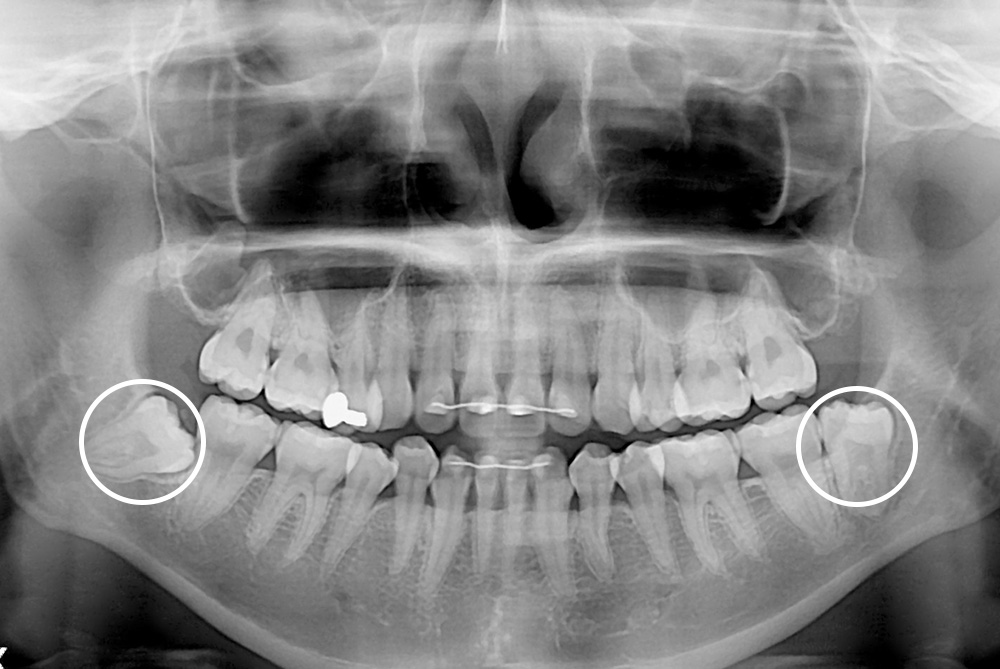

[사랑니] 매복 사랑니 발치

치료전 : 2019-03-14